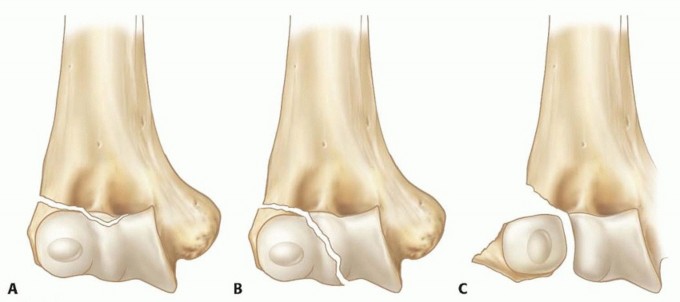

Displacement-based classifications (e.g., Jakob classification) are highly pragmatic for operative decision-making, focusing on the integrity of the articular cartilaginous hinge:

* Stage I: Nondisplaced or minimally displaced (<2 mm). The articular hinge of cartilage remains totally intact, acting as a tether that prevents rotation and displacement.

* Stage II: Displacement between 2 mm and 4 mm. The articular cartilage hinge is breached or stretched, indicating structural failure, but the fragment has not yet undergone significant multiplanar rotation.

* Stage III: Displacement greater than 4 mm with multidirectional rotation of the fracture fragment. The unopposed pull of the extensor musculature displaces the fragment distally, laterally, and rotates it up to 180 degrees out of the joint, rendering closed reduction impossible.